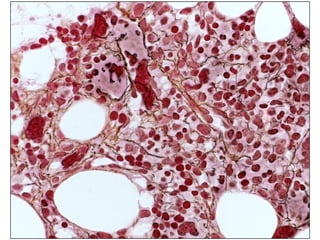

Histocellularity markedly increased (60-70%) blasts infiltration. pleomorphic blasts abundant cytoplasm.  Blasts strongly positive for immunoperoxydase, CD34 CD117 dim. Histological diagnosis: acute myeloid leukemia (AML) with maturation

Histocellularity markedly increased(60-70%) blasts infiltration. pleomorphic blasts abundant cytoplasm.  Blasts strongly positive for immunoperoxydase, CD34 CD117 dim. Histological diagnosis: acute myeloid leukemia (AML) with maturation